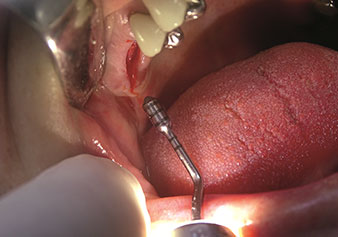

Preparazione del pavimento del seno mascellare e del rialzo della membrana di Schneider (strumento Z35P)

Fig. 4: Preparazione del pavimento del seno mascellare e del rialzo della membrana di Schneider (strumento Z35P).

Dopo la preparazione dei seni mascellari con il corrispondente set di strumenti (Fig. 3), il nuovo strumento Z35P (Fig. 4) viene utilizzato per sollevare la membrana idrodinamicamente. Lo stesso set di strumenti può essere utilizzato anche per la preparazione piezochirurgica della sede dell’impianto in diametri crescenti (Figure 3 e 4 inserite grazie alla gentile concessione del Dott. Mario Kirste, Frankfurt/Oder).